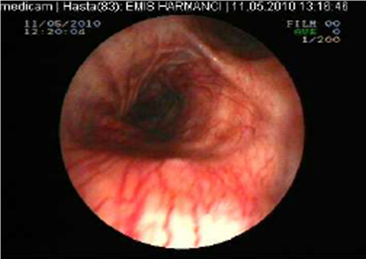

Tuberculosis treatment was initiated with isoniazid with a daily dose of 300 mg, rifampicin 600 mg, ethambutol 1500 mg, pyrazinamide1500 mg and these doses were planned to be continued for further 6 months. Clinical remission started after two weeks of the treatment period. Control sputum samples were obtained and control culture analysis was performed at the end of two months therapy. Both of these were negative for AFB. We observed significant clinical and radiological remission at the end of three months of this treatment period. Control FOB examination performed in the sixth month of the therapy demonstrated that the white colored necrotic lesions disappeared completely and significant improvement was observed (Figure 3 and Figure 5, respectively).

Figure 3

Necrotic lesions were disappeared at the end of six months treatment